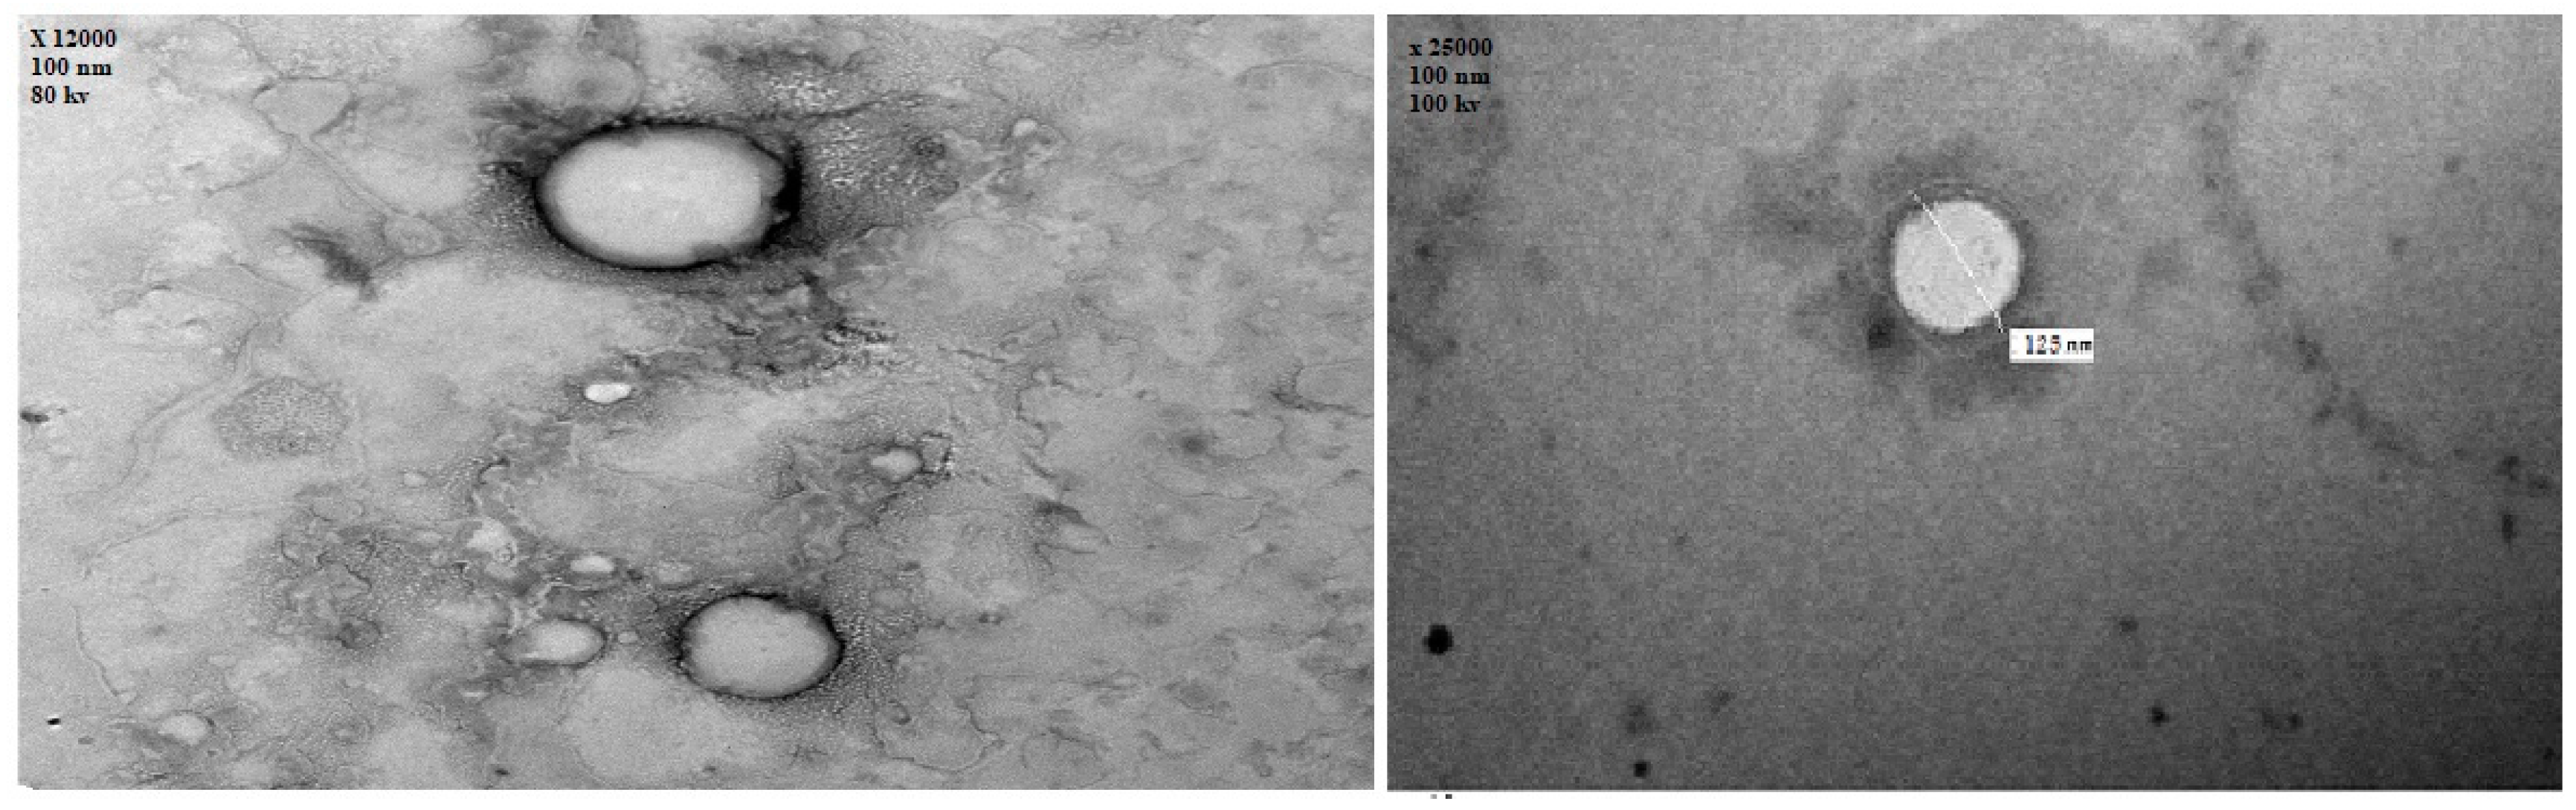

3.4. Morphological Evaluation